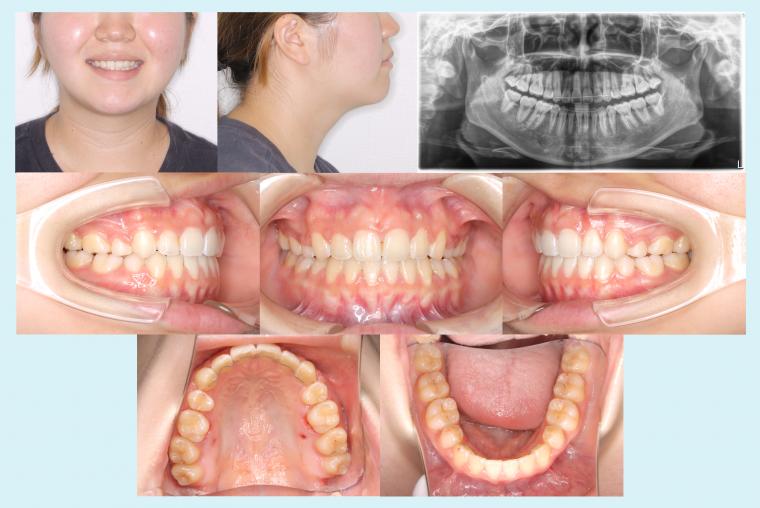

♯48 八重歯を治療した症例